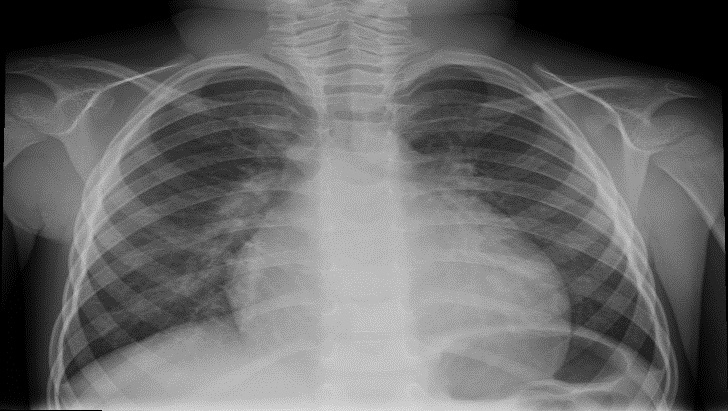

Ante estos hallazgos clínicos se realizó una radiografía de tórax observándose cardiomegalia e infiltrados peribroncovasculares bilaterales (Fig. 1). La analítica sanguínea presentó 0,24 ng/ml de troponina, NTproBNP 9030 pg/l, pH 7,27, lactato 1,70 mmol/l, bicarbonato 13,5 mmol/l, exceso de base -12,3 mmol/l y cetonemia 6,1 mmol/l; el resto de los valores están dentro de los límites normales. Se realizó un electrocardiograma de superficie en el que se observa taquicardia sinusal y ondas T positivas en derivaciones precordiales derechas (Fig. 2).